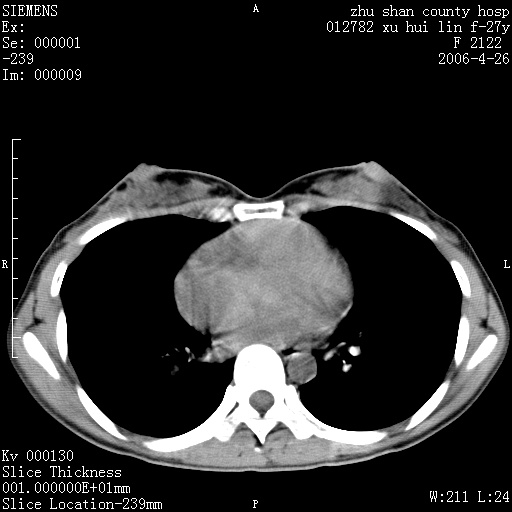

女性 病人 27岁!本院职工家属,五月前因感冒透视发现病变,ct示:左肺下叶背段感染性病变。经过半月规范抗生素治疗后复查病变无明显变化,后行四月规范抗痨治疗,复查无明显变化,后复查无效!请大家帮忙看看!

右肺下叶背段见片状高密度区,边界不清,密度不均,无钙化及空洞影,背段支气管通畅。所见层面肺门及纵隔内未见明显肿大淋巴结影。

女性 病人 27岁!本院职工家属,五月前因感冒透视发现病变,ct示:左肺下叶背段感染性病变。经过半月规范抗生素治疗后复查病变无明显变化,后行四月规范抗痨治疗,复查无明显变化,后复查无效!

诊断:首先还是考虑为慢性炎症。

结核虽然好发于下叶背段,但周围无明显卫星灶,化验结果怎样?